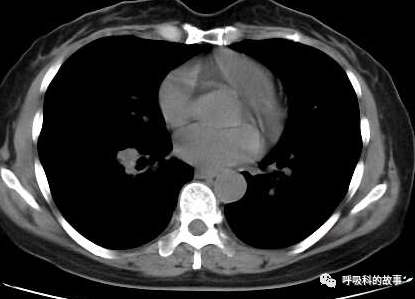

1個月前,黃女士來到了杭州市第一人民醫院呼吸科,找到我看病,我給她複查了肺部CT,如下:

初一看,好像就是普通的肺炎,可是為什麼相隔兩個月在同一部位反覆發生呢?另外,右下葉肺門較左側明顯增大,感覺到管腔似乎也不是那麼清爽,於是我繼續開啟縱隔窗繼續檢視影像情況。

這一看嚇我一跳,患者右下葉支氣管腔內有高密度影,這讓我首先想到的就是支氣管異物堵塞管腔,從而引起阻塞性肺炎。於是我在認真檢視後,嚴肅地對患者說要住院。黃女士可能一來工作繁忙,二來對我的診斷可能表示懷疑,因為她記憶裡沒有誤吸的事件發生,三來以前的CT報告也沒有提示支氣管異物,於是要求繼續口服藥物治療。